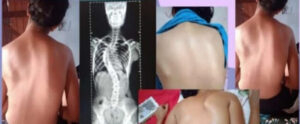

Mãe desesperada busca ajuda para cirurgia de adolescente com escoliose em Ourolândia